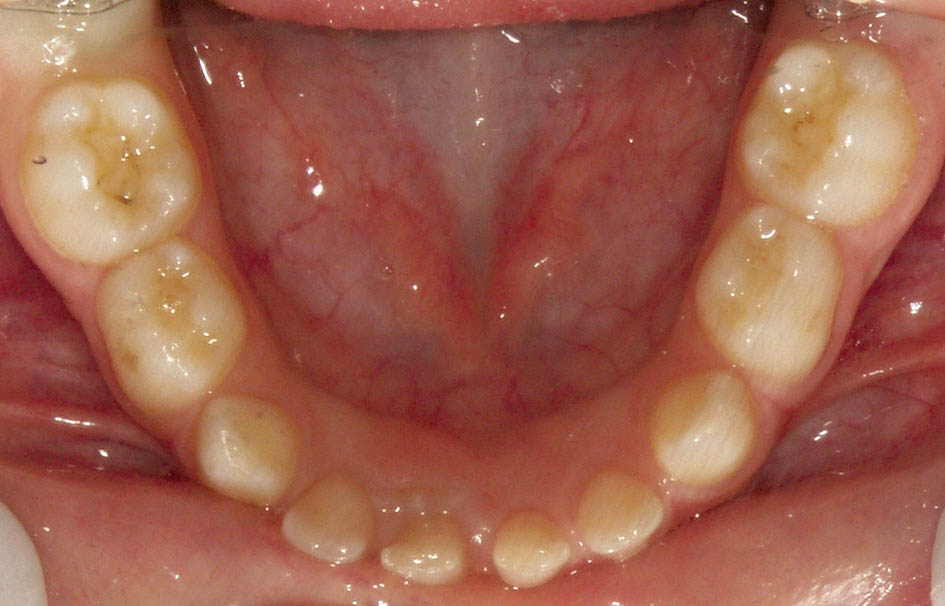

2. در اوایل مرحله دندانی شیری-دائمی تکامل زائده آلوئلی را داریم که منجر به افزایش عرض بین کانینی میشود.

شکل 6-5 : سایز کوچک انسیزورهای پایین